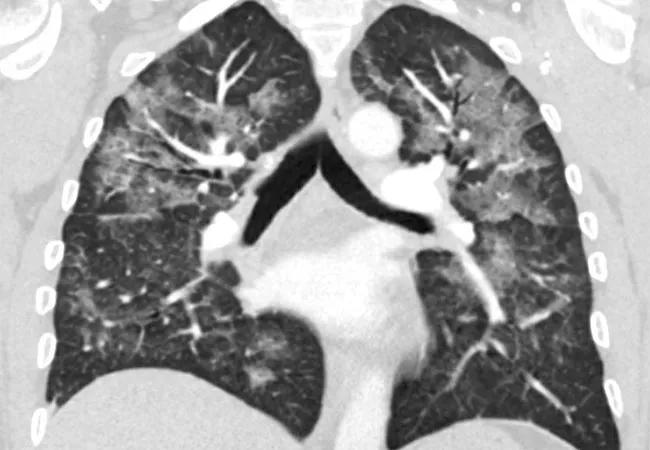

A CT chest was obtained, revealing diffuse patchy, nodular and confluent ground glass opacities with interlobular and intralobular septal thickening and dependent basilar atelectasis (Figure 1A, B). Stains and culture of sputum were negative for infectious etiologies. Bronchoscopy with bronchoalveolar lavage showed macrophage predominant lavage fluid, and transbronchial biopsy revealed focal organizing pneumonia (Figure 2A, B).

Figure 1A-B